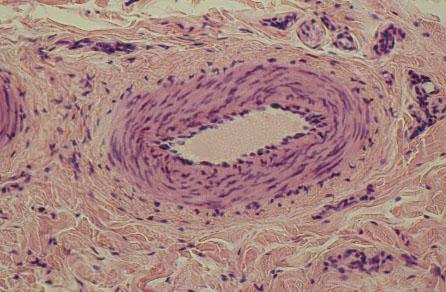

VI-30 (5) Slide 42, Lip (H&E). A muscular artery is shown with tunica intima (endothelial cells) tunica media of smooth muscle layers, and thin adventitia